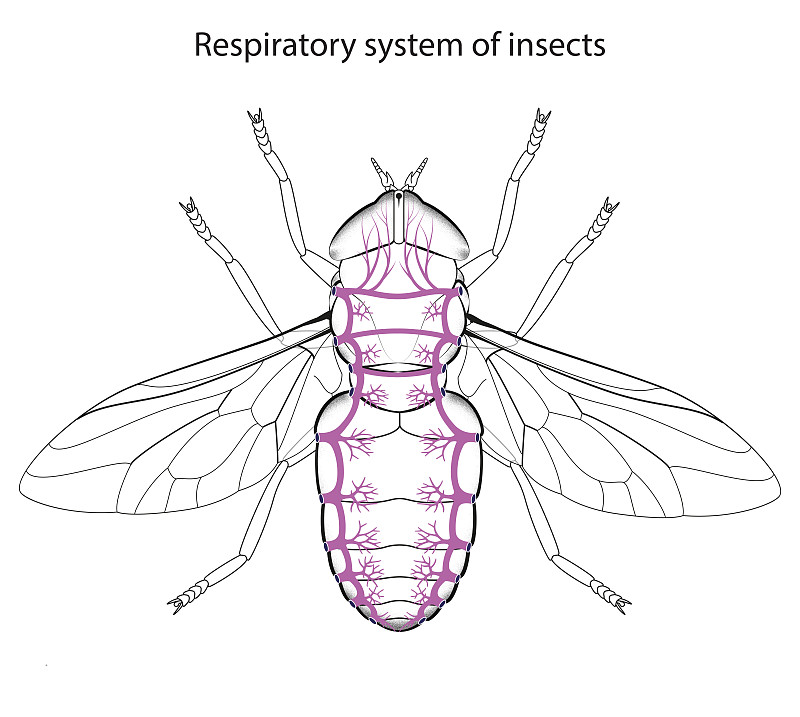

昆虫呼吸系统详情